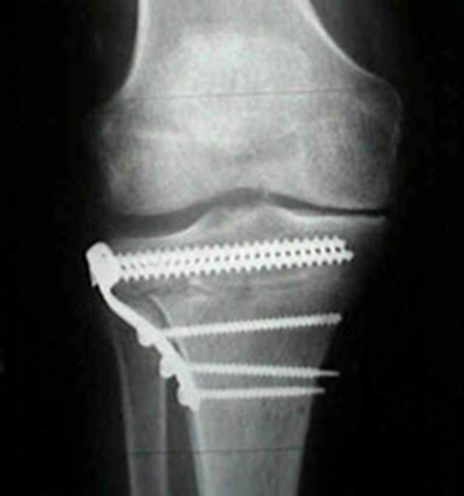

Thoái hoá khớp là hậu quả của quá trình cơ học và sinh học làm mất cân bằng giữa tổng hợp và huỷ hoại của sụn và xương dưới sụn.